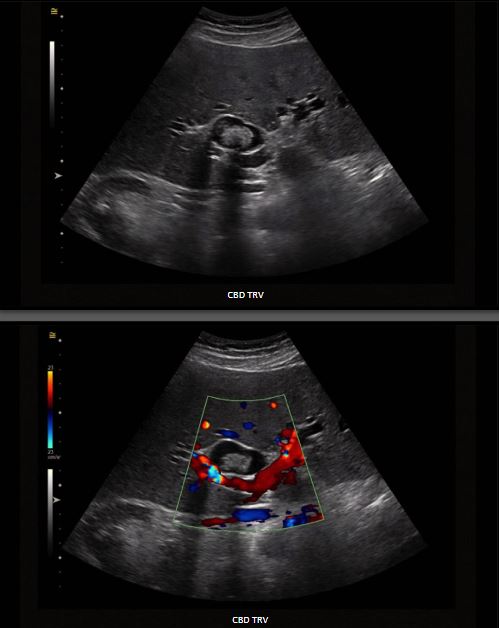

T scan is frequently obtained in evaluating abdominal pain; however, like transabdominal ultrasound it has limited sensitivity in detecting CBD stones. Many biliary stones lack calcium, and on CT appear similar in echogenicity to the surrounding bile, hindering the diagnosis. Definitive diagnosis of choledocholithiasis is made with advanced imaging, consisting of magnetic resonance cholangiopancreatography (MRCP), endoscopic retrograde cholangiopancreatography (ERCP), endoscopic ultrasound (EUS), intraoperative cholangiography (IOC), and intraoperative ultrasound (IUS). The best method for the diagnosis is controversial, as each modality has benefits and shortcomings.The treatment of choledocholithiasis varies locally, according to the practitioner's skills and equipment availability. The cornerstone of therapy is removing the biliary stone and early recognition and treatment of complications (jaundice, acute pancreatitis, and acute cholangitis).107-109The large shadowing structurein the CBD represents a stone.CBD TRVCBD TRV99